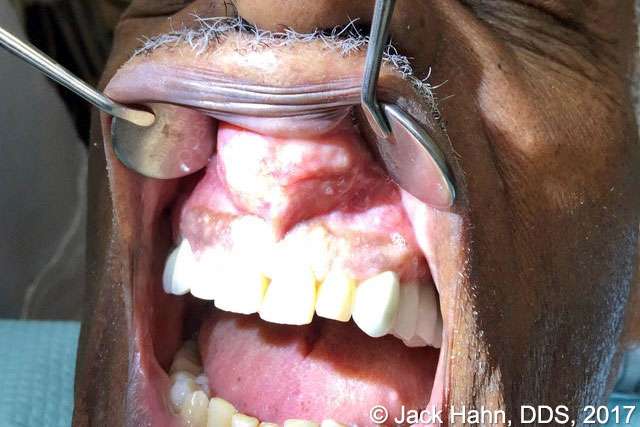

A patient presented to Jack Hahn, DDS, for a large swelling under the upper lip—a nasopalatine cyst (see Figure 1). Dr. Hahn opened the cyst with a scalpel, draining a substantial amount of exudate (see Figure 2). He then used his LightScalpel CO2 laser to sanitize the remaining cystic cavity, which also helped to manage the bleeding. He then sutured the cystic cavity shut (Figure 3). At six weeks post-operation the tissue is healing well (Figure 4).